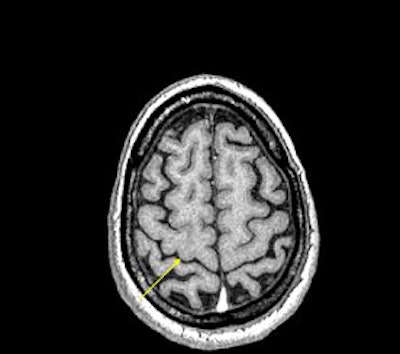

The reason for this reduction may be attributable to the increased iron content in these areas, Haacke explained. The iron can act like a paramagnetic contrast agent and shorten T1. SWI can use this phase difference to enhance the T1 contrast in an image (see below).

| An example of increased brain iron in gray matter changing local T1 as conceived by Robert Ogg, Ph.D., St. Jude Children's Research Hospital, Memphis, TN. The arrow shows the gray matter in the central sulcus. Note the poor contrast in the T1-weighted image and the excellent contrast in the phase image. Data collected on a 1.5-tesla system (Vision, Siemens Medical Solutions, Malvern, PA) with a TE = 40 msec by Larry Gates, Ph.D., Dalhousie University, Halifax, Nova Scotia. |